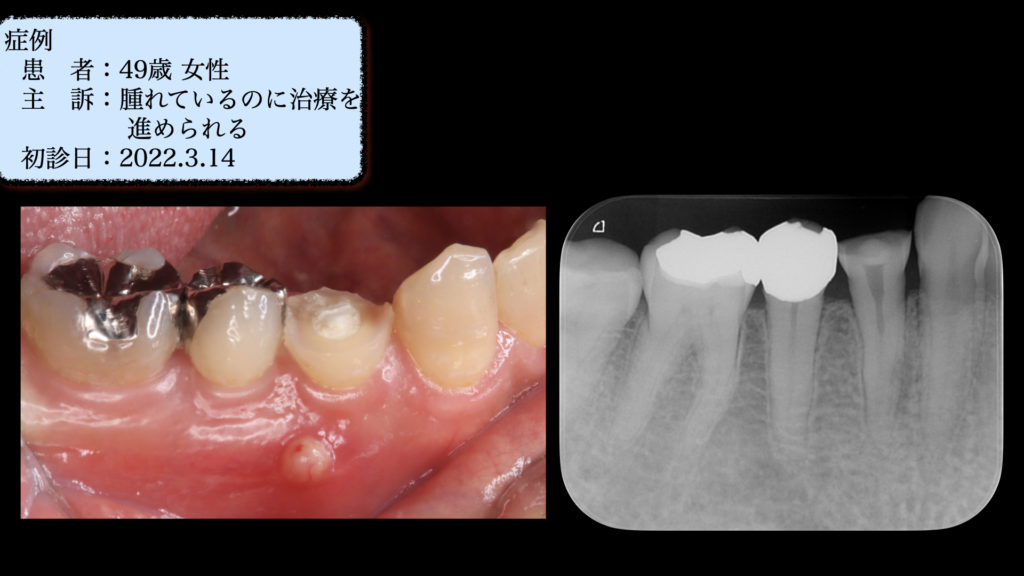

他院の根管治療に納得いかずに当院を受診

他院で根管治療中だが、なかなか腫れが引かないが、このまま治療を進めていく。と言われ心配で転院された患者さんでした。 そんなに時間がかかっているので、歯の中に穴が開いていたり・歯が折れている可能性も説明し、マイクロスコープを使用した精密根管治療をおこなうことにな … 続きを読む 他院の根管治療に納得いかずに当院を受診